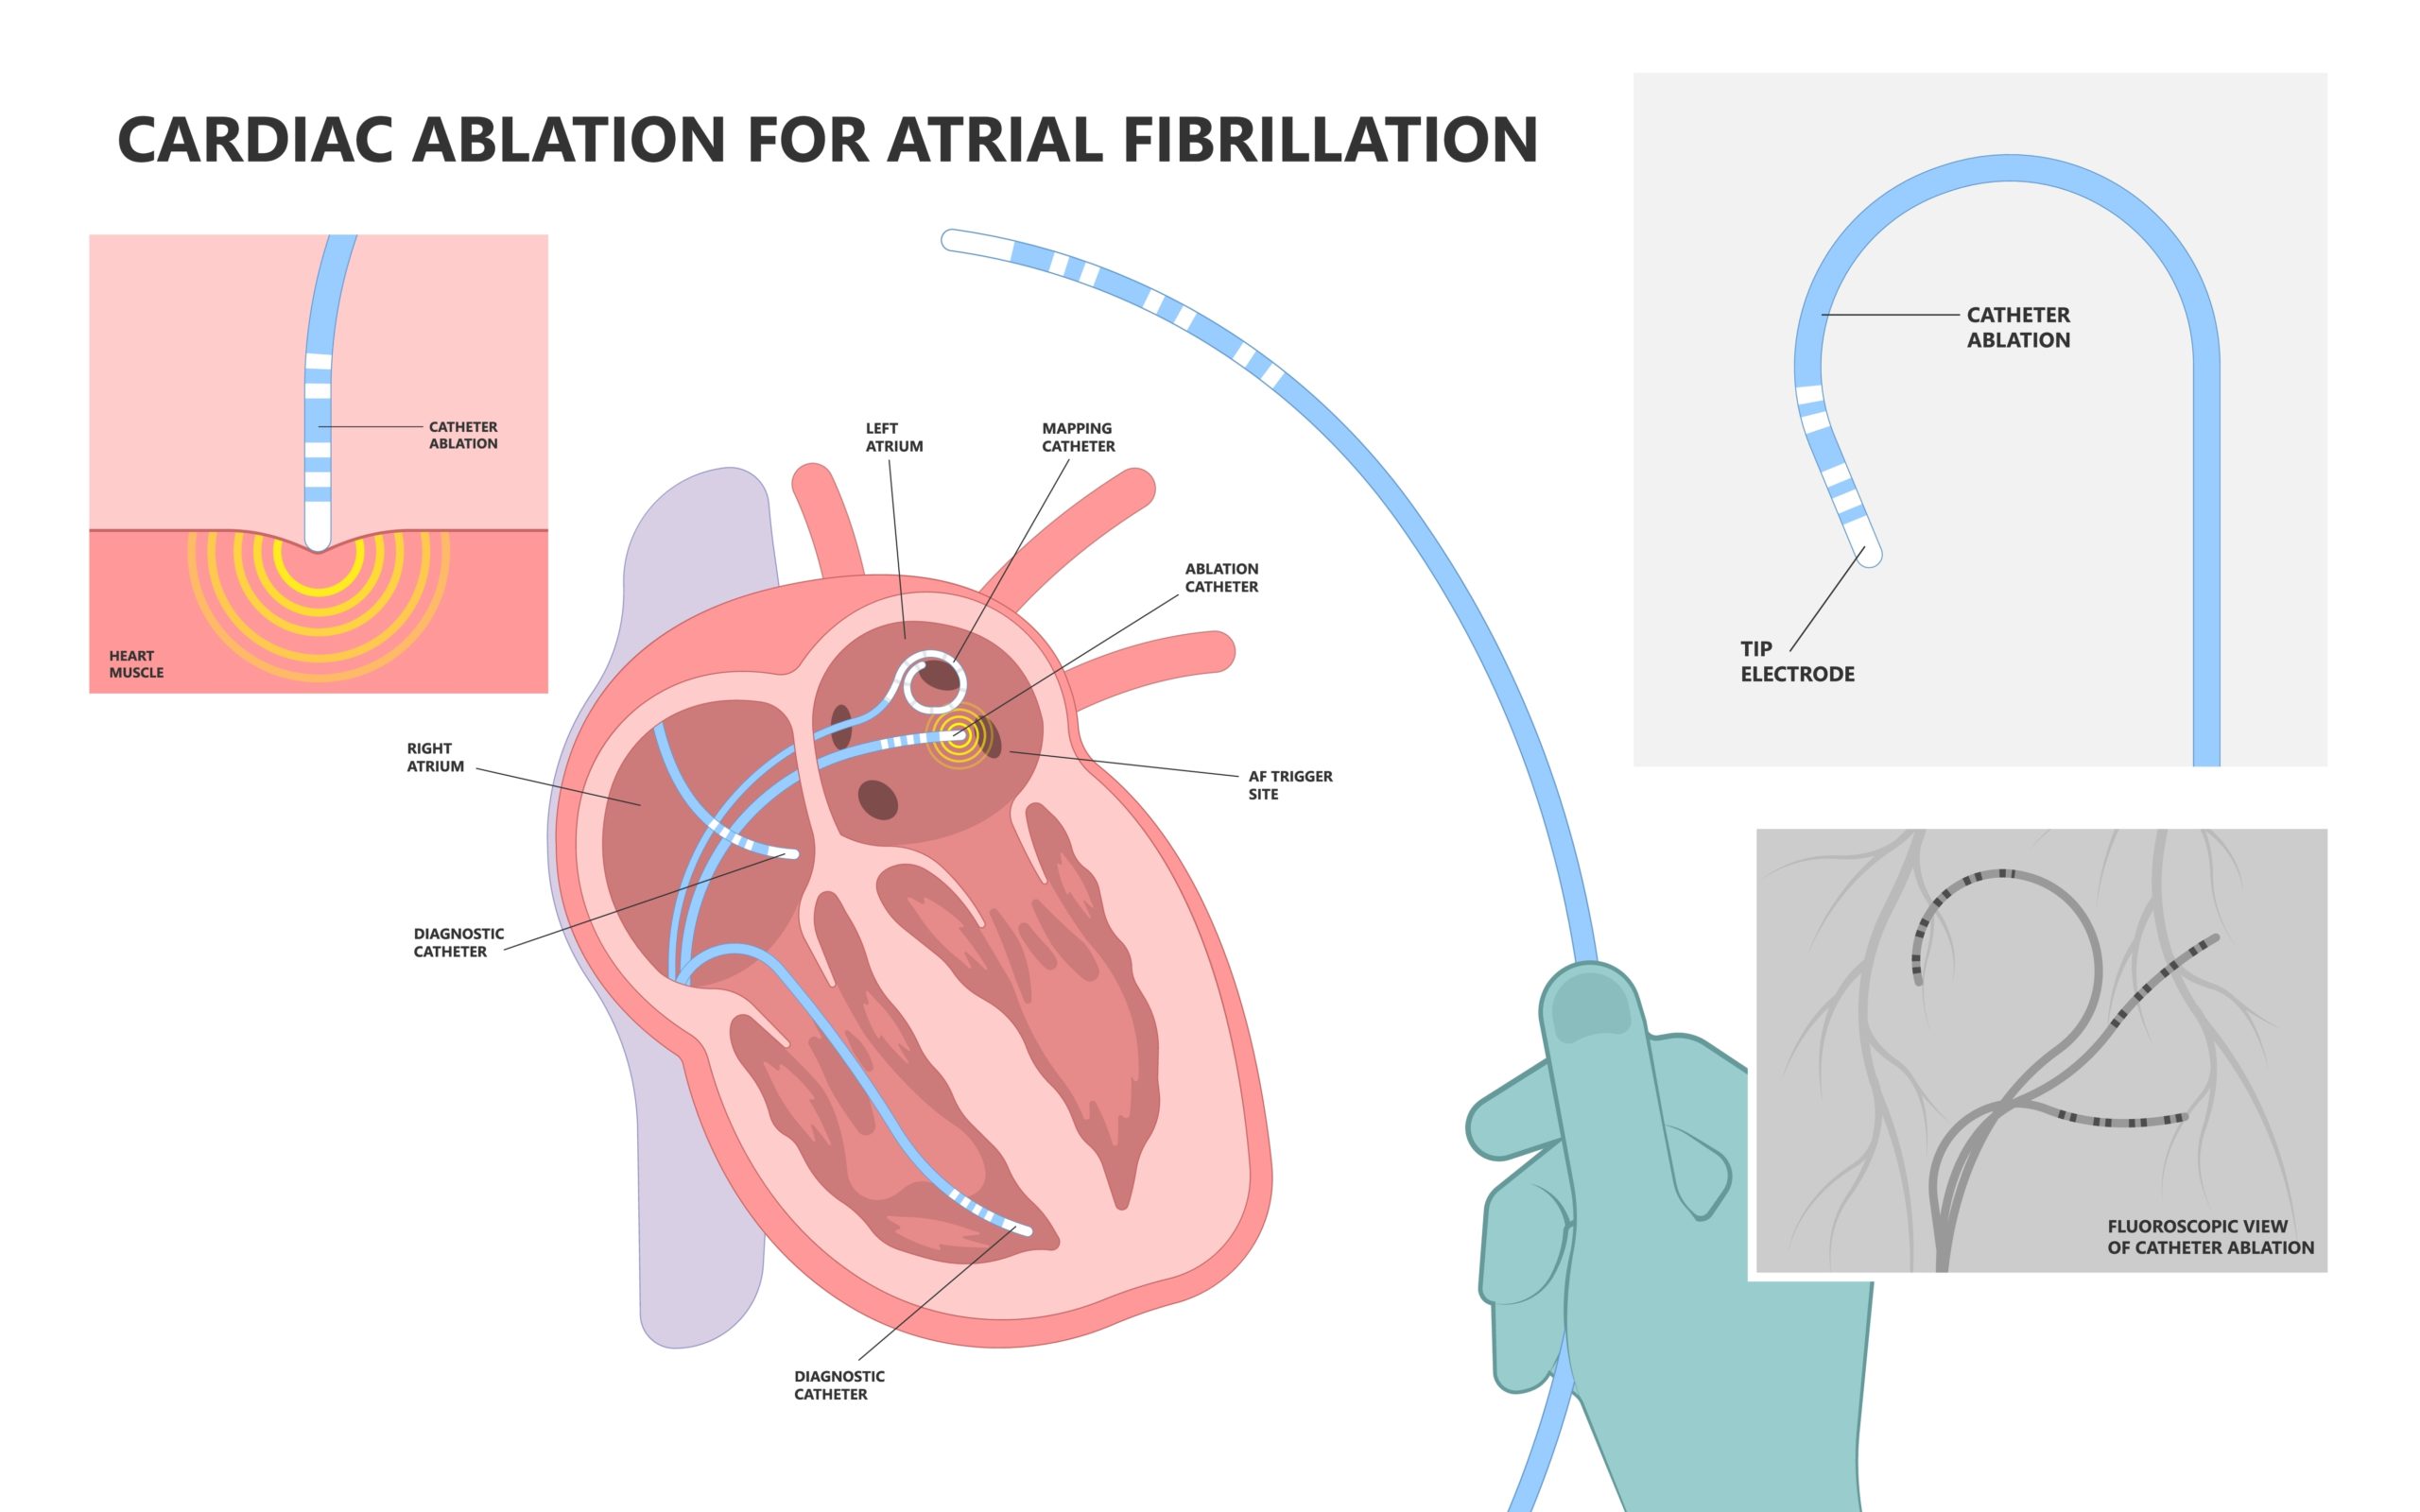

catheter ablation

The primary goal of catheter ablation (CA) in patients with atrial fibrillation (AF) is to reduce symptom burden and ...